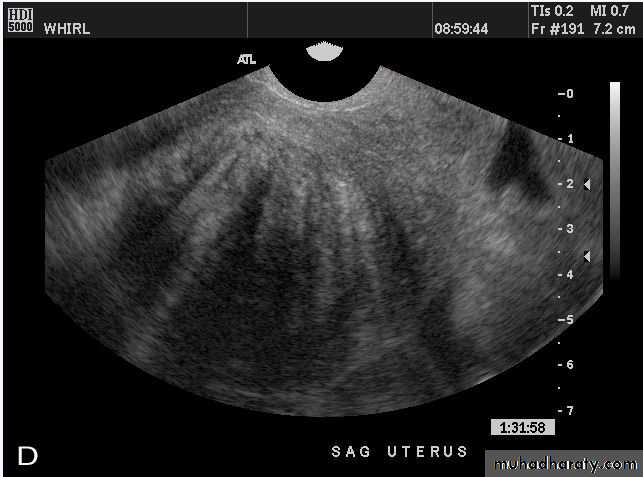

Normal Uterus

Normal Uterus in longitudinal view

Sagittal US image of the uterus obtained during the secretory phase of the menstrual cycle shows a thickened, echogenic endometrium (cursors).